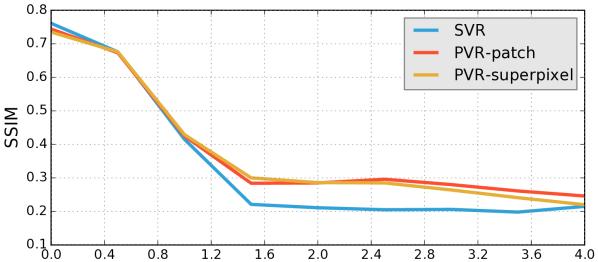

Reconstruction of Adult Brain MRI: Experiments on adult brain MR data using the Brainweb database [34] included introducing synthetic non-rigid motion artifacts as described in Sec. IV. Example slices of standard planes of original and corrupted data are depicted in Fig. 9. Comparative experimental results of SVR and PVR reconstruction methods are shown in Fig. 10 for PSNR, SSIM and CC. For all metrics, PVR shows an improved performance over SVR, particularly in presence of deformations with higher skewing angles. Further, we observe that superpixel-based PVR achieves similar performance as PVR using arbitrary square patches, while requiring a lower amount of input patches.